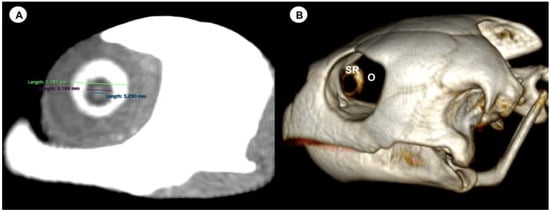

- Dorsal and ventral arch length: the thickness of the upper and lower regions of the scleral ring, with the corneal and scleral margins (Figure 2B).

- Width of the dorsal and ventral arches of the scleral ring, that is, of the upper and lower parts of the lateral portion of the ring (Figure 2A).

- Height of the eyeball or distance between the most dorsal and the most ventral portion of the eye (Figure 3B).